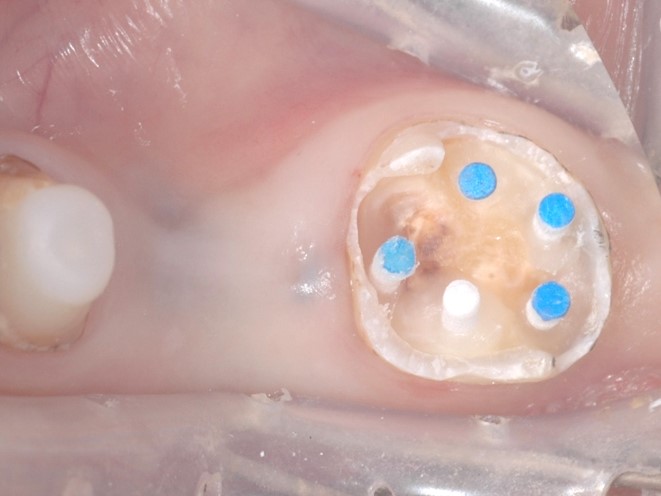

次にファイバーポストを5本スーパーボンドにて植立します。(下写真)